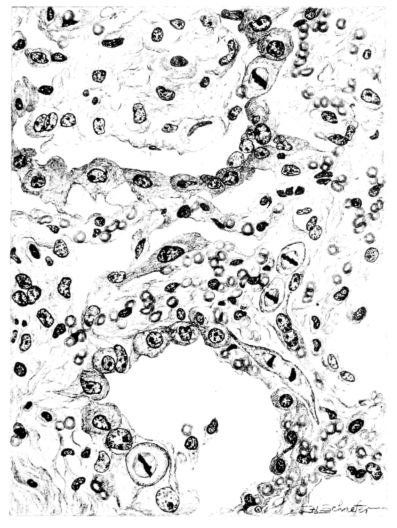

A more striking picture, however, even than this aplastic alveolar exudate appears in the terminal bronchioles. In many instances, these are conspicuous on account of their size, for they are dilated to form prominent, often irregular, sacs (Fig. XV). The distention of these terminal bronchioles may be so great that the surrounding alveoli are compressed. What makes them even more conspicuous is their lining, once epithelium, but now a swollen, thick, homogeneously staining material, with complete loss of architecture; the material forms (with hematoxylin and eosin) a red band limiting the lung tissue and sharply demarcating it from the exudate within the bronchioles (48, 92). However, this ribbon of red, often thickened by fibrin deposition, is not always pure, for bacteria thrive in the dead tissue. They occur singly, paired, in chains, and also as circumscribed, dense masses which in size and position, simulate nuclei (162) (Fig. XVI). This same hyalinization of the epithelium, it will be recalled, occurs in the larger bronchi (Fig. V), and there, too, bacteria frequently develop in the dead tissue (Fig. VIII). In the smallest bronchiolar ramifications, acute epithelial necrosis is not infrequently encountered, even when the surrounding lung tissue is relatively normal (Fig. XVI). That the process does not stop with the epithelium, but, as in the larger bronchi, may extend through the entire structure of the bronchioles, is manifest. Even the alveolar walls may be involved and frequently homogeneous pink or red bands, now the phantom of the former viable lung tissue, mark the presence of the old wall of the alveolus (Fig. XVII). Occasionally, some architecture remains in this pink ribbon and then the involvement seems to be primarily in the vessels of the wall. Not all the vessels are involved, and next to a hyaline thrombus in one, there may be fresh blood, usually red blood, in its neighbor. The alveolar epithelium is usually denuded and thus accentuates the intensity of the change.

15There is considerable evidence to support the view that the disease spreads from bronchus to bronchus, and in keeping with this view, various stages in the inflammatory processes are more readily determined in these smaller structures than in the trachea. Furthermore, it must be emphasized that even the mildest and the most extreme of these stages are not infrequently encountered in the same lung. The earliest lesion is manifested by an increased homogeneity of the protoplasm of the epithelial lining of the bronchus. The cell protoplasm loses its normal granulation and the nucleus, somewhat darker than usual, becomes conspicuous on a red base (Fig. V). In the lumen of such a tube a serous exudate, perhaps mixed with mucus, is encountered, and there is some spreading apart of the surrounding muscular tissue with engorgement of the vessels. This picture merges gradually into one where the epithelium appears as a homogeneous, red-staining ribbon, devoid of nuclei, often exfoliated, in part at least, from the underlying submucosa (92). The change is traceable through the larger bronchi, even to the ducti alveolares, and not infrequently, bacteria, either as a diffuse, minute dotting or in the form of circumscribed, colony-like formations, are spread through the red, ribbon-like strand (Fig. XVI). With the exfoliation of the epithelial lining, the submucous vessels become more and more conspicuous and may bulge into the lumen of the tube (Fig. VI). That they actually weep into the lumen is proved by the presence of red blood cells in the exudate, now rich in mucus, broken-down nuclei, and desquamated cells. The necrotizing process may not extend deeper than the epithelial lining as is the status described above (140, 162), but it also frequently involves the underlying submucous and muscular layers, so that these lose their identity and stand out as homogeneous masses, in which fragmented nuclei and bacterial accumulations are prominent. Such deeper necrotizing areas may be focal (Fig. VII), or may involve the entire circumference of the tube (Fig. VIII). Occasionally, the epithelium, now dead and staining homogeneously, is lifted from the underlying submucosa in the form of a blister (66), and has very much the same appearance as the well known, early reaction which follows the application of croton oil to the rabbit’s ear. Where this occurs, the submucosa is less involved, as though the necrotizing agent had not penetrated to the same depth and the serous reaction beneath were actually a beneficent exudate. These blisters are in contrast with the deeper areas where the fibrinous mass, mixed with the dead tissue, forms an intensely staining ring or band, which extends through the bronchiolar wall even to the surrounding alveoli.